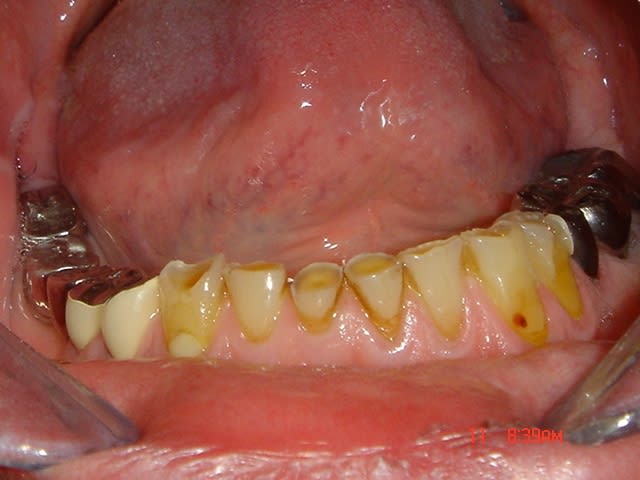

Bonjour, tout est ds le titre. Le cas est severe, voir photos, mais le patient est cooperant et agreable. [email protected]

La vache, il est joli celui là. Je suis en plein dans un cas de ce style (mais pas encore aussi atteint quand même). J'attends que les implants s'ostéointègrent.

Je ne trouve pas ce cas si désespéré que ça.

Le bas est pas si mal je trouve, et constitue une bonne base pour traiter le haut au moins dans un premier temps.

Joli cas..... je ne vais pas repondre à la question d'un "quelqu'un sur paris" mais par contre il y là matiere à discutter des solutions:

3/ à priori ce patient a une bonne hygiene et il me semble qu'au niveau qualité du support osseux il est pas mal sinon y'a belle lurette que ses dents se seraient barrées. Donc que du positif.